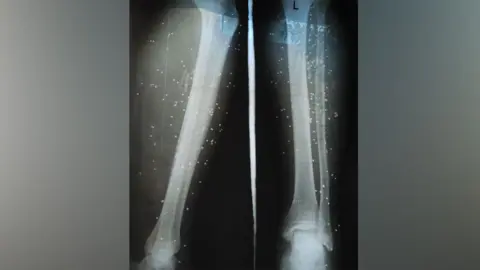

Nearly half of those surveyed reported delays in treatment leading to severe complications among patients, including amputations and lifelong disabilities.